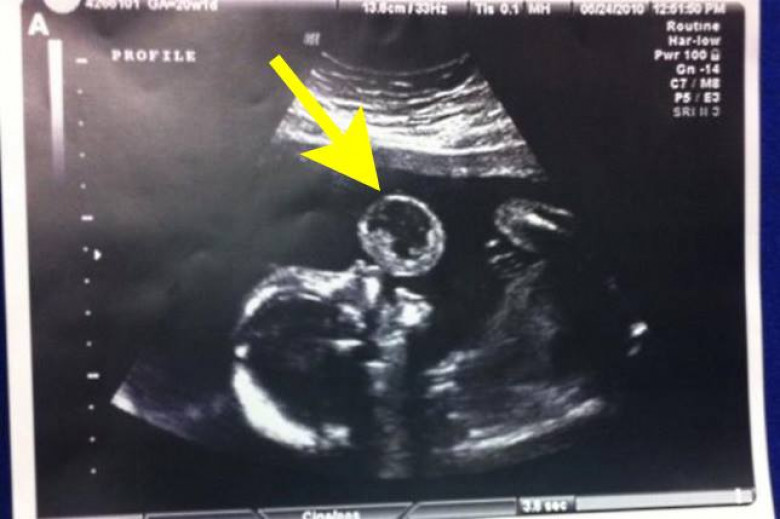

Տամմի Գոնսալեսն անհամբեր սպասում էր իր փոքրիկի ծննդյանը: Բայց երբ նա գտնվում էր հղիության 17-րդ շաբաթում, բժիշկները նրան տհաճ լուր հայտնեցին: Նրանց շատ էր անհանգստացրել ուլտրաձայնային հետազոտության արդյունքները: Նկարում թվում էր, թե երեխան փուչիկ է փչում:

Չնայած առաջին հայացքից այդպիսի տեսարանը կարող է զվարճալի թվալ, բայց իրականում դա կարող էր մեծ խնդիրների պատճառ լինել: Աղջկա մոտ մեծ չափերի տերատոմա էր զարգացել. Բարորակ ուռուցքի տեսակ: